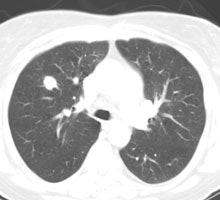

True negative PET scan: The patient in the scan below had a 1.5 cm left upper lobe nodule (shown below) that could be retrospectively identified on a prior CT scan at which time it measured only 4 mm. A PET scan was performed (below right), but demonstrated no uptake in the lesion (some cardiac activity can be seen more anteriorly). Because the nodule had enlarged from a prior exam, the nodule was resected and found to be a granuloma. Nodules larger than 1.5 cm that are negative on PET scans have a highly likelihood for representing benign or indolent lesions. |